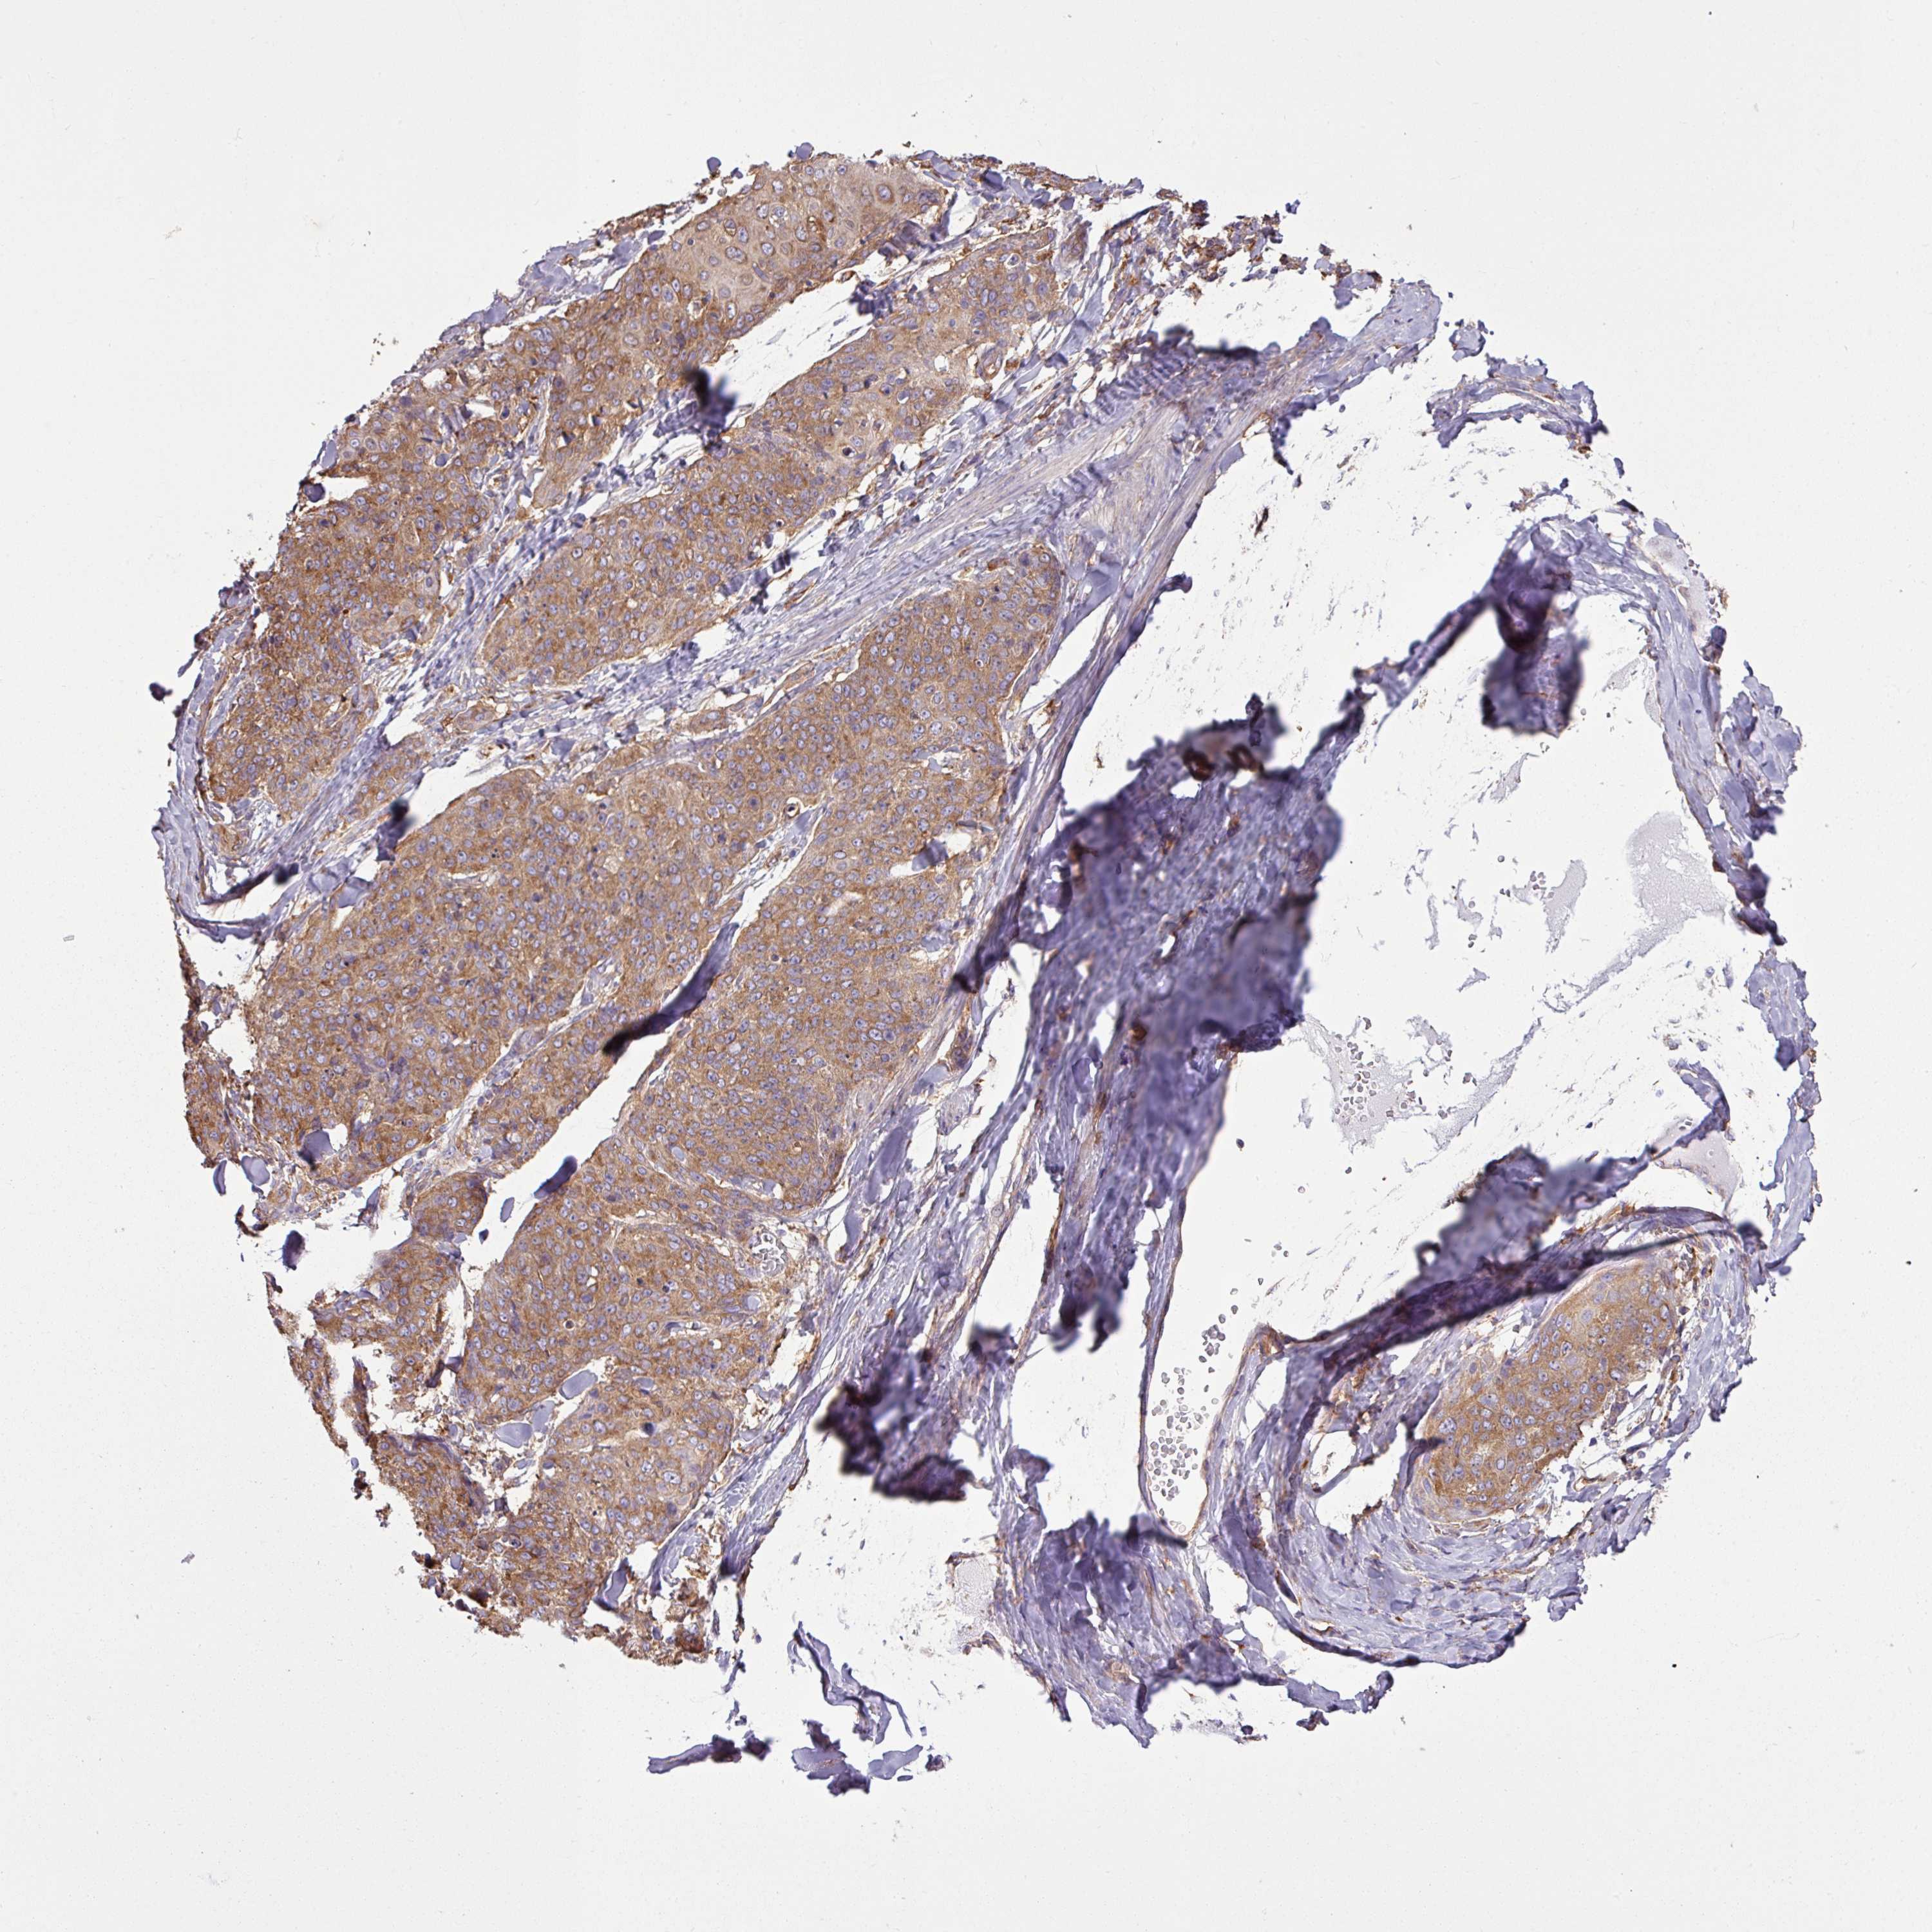

Basal cell and squamous cell cancer

SKIN CANCER - Protein expressioni

A mouse-over function shows sample information and annotation data. Click on an image to view it in a full screen mode. Samples can be filtered based on level of antibody staining by selecting one or several of the following categories: high, medium, low and not detected. The assay and annotation is described here.

Antibody stainingi

Antibody staining in the annotated cell types in the current human tissue is reported as not detected, low, medium, or high, based on conventional immunohistochemistry profiling in selected tissues. This score is based on the combination of the staining intensity and fraction of stained cells.

Each image is clickable and will lead to virtual microscopy that enables deeper exploration of all samples and also displays staining intensity scores, fraction scores and subcellular localization as well as patient and tissue information for each sample.

Antibody HPA049854

Antibody HPA056520

Staining

High

Medium

Low

Not detected

Intensity

Strong

Moderate

Weak

Negative

Quantity

>75%

75%-25%

<25%

None

Location

Nuclear

Cytoplasmic/membranous

Cytoplasmic/membranous,nuclear

Basal cell carcinoma

Squamous cell carcinoma, NOS

Squamous cell carcinoma, metastatic, NOS